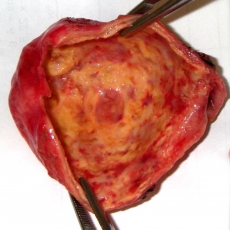

This inflamed gall bladder was removed surgically. It has been opened and the pus and stones cleaned away to display the inflamed inner lining.Gallstones can lead to acute inflammation of the gallbladder. This is called cholecystitis (pronounced: ko-lay-sis-tie-tis; the word literally means inflammation of the gall bladder; “chole” refers to bile, “cyst” means a fluid-filled sack, and “-itis” refers to inflammation).

This inflamed gall bladder was removed surgically. It has been opened and the pus and stones cleaned away to display the inflamed inner lining.Gallstones can lead to acute inflammation of the gallbladder. This is called cholecystitis (pronounced: ko-lay-sis-tie-tis; the word literally means inflammation of the gall bladder; “chole” refers to bile, “cyst” means a fluid-filled sack, and “-itis” refers to inflammation).

Acute cholecystitis is a medical emergency and requires admission to hospital. Treatment has conventionally involved pain killers and antibiotics to settle the acute inflammation, followed several weeks later by an operation to remove the gall bladder. Of late, if the diagnosis has been made promptly, surgeons may resort to immediate surgery.

Acute cholecystitis caused by aggressive bacteria can cause the gall bladder wall to rot and disintegrate, and the gall bladder may then burst into the abdominal cavity or into an adjacent bit of bowel.

If there have been repeated attacks of inflammation, the gall bladder becomes chronically inflamed, shrunken and scarred. This is called chronic cholecystitis. If the outflow from the gall bladder is totally blocked by a stone it may become a bag full of stagnant bile (a mucocoele) or a bag of pus (empyema).